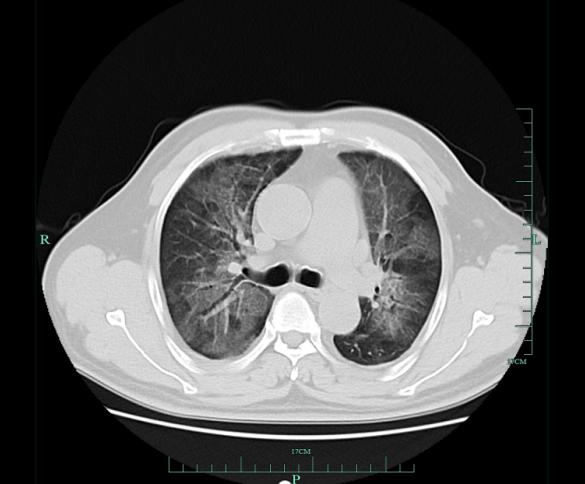

患者的肺影像

肺部是在当地医院进行的 CT 发现毛先生的双肺大规模变白。当地医院进行抗感染、消炎等对症治疗后,他的病情并没有明显改善。当地专家建议,他要抓紧浙江大学第一医院的早期诊断,在预防肺病方面有丰富的经验。